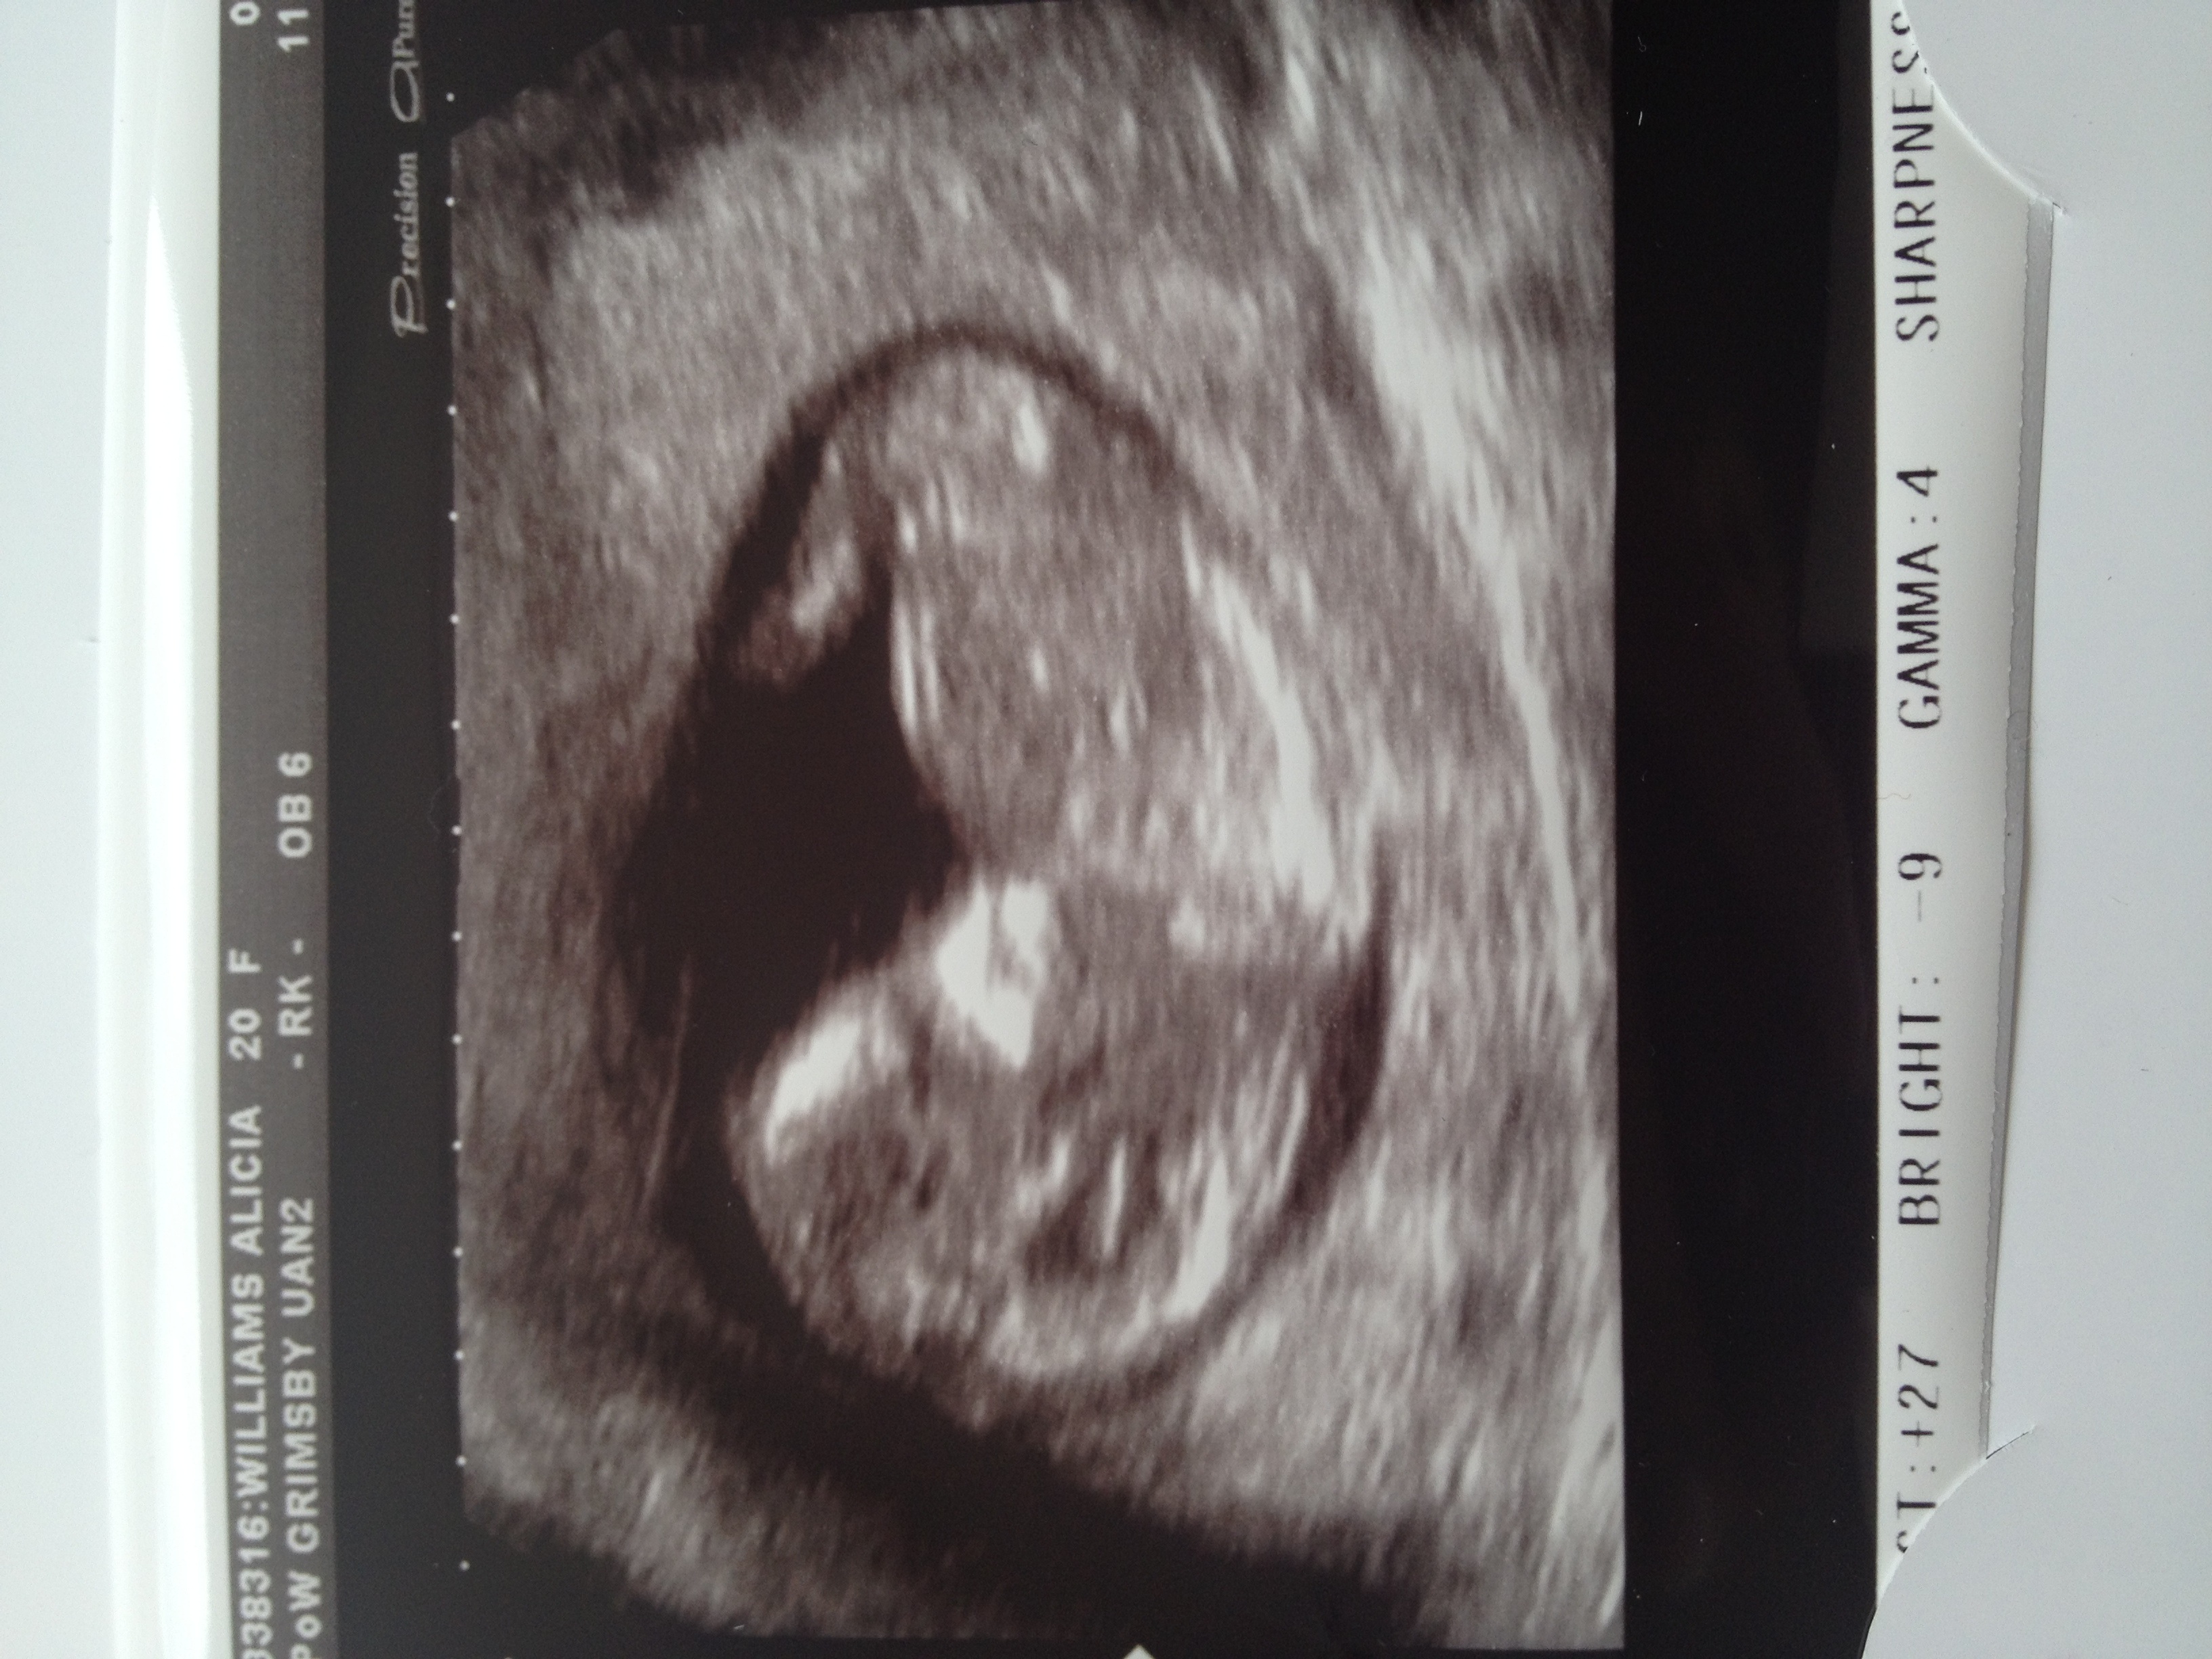

Hi I'm new to this but I just can't wait to find out if I'm having another boy or a girl. Would anyone like to have a guess as to what they think it may be? Thanks ladies!Attachment 13844

No gender clues in this shot! Do you have any others?

No nub, but if you look into the skull theory, possibly boy, its a little early to tell. sorry! :)